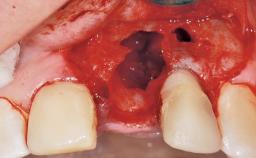

Late Flapless Placement of an Implant in a Maxillary Left Central Incisor Site

A 39-year-old male patient presented with a chief complaint of discomfort and gingival discoloration around his maxillary left central incisor. He was in good general health and was a non-smoker. His past dental history was significant because of the traumatic fracture of tooth 21 in a sporting accident at age 13. Initial dental treatment included endodontic therapy and a full-coverage restoration. The patient became symptomatic 5 years later, when structural failure of the tooth resulted in the dislodgment of the crown. Endodontic retreatment, apical surgery, and post-and-core restoration were performed.

Bone Augmentation Horizontal|Staged

Augmentation Materials Xenogenous|Membrane

Soft Tissue Grafting Simultaneous

Bone Volume Deficient horizontally, requiring prior grafting